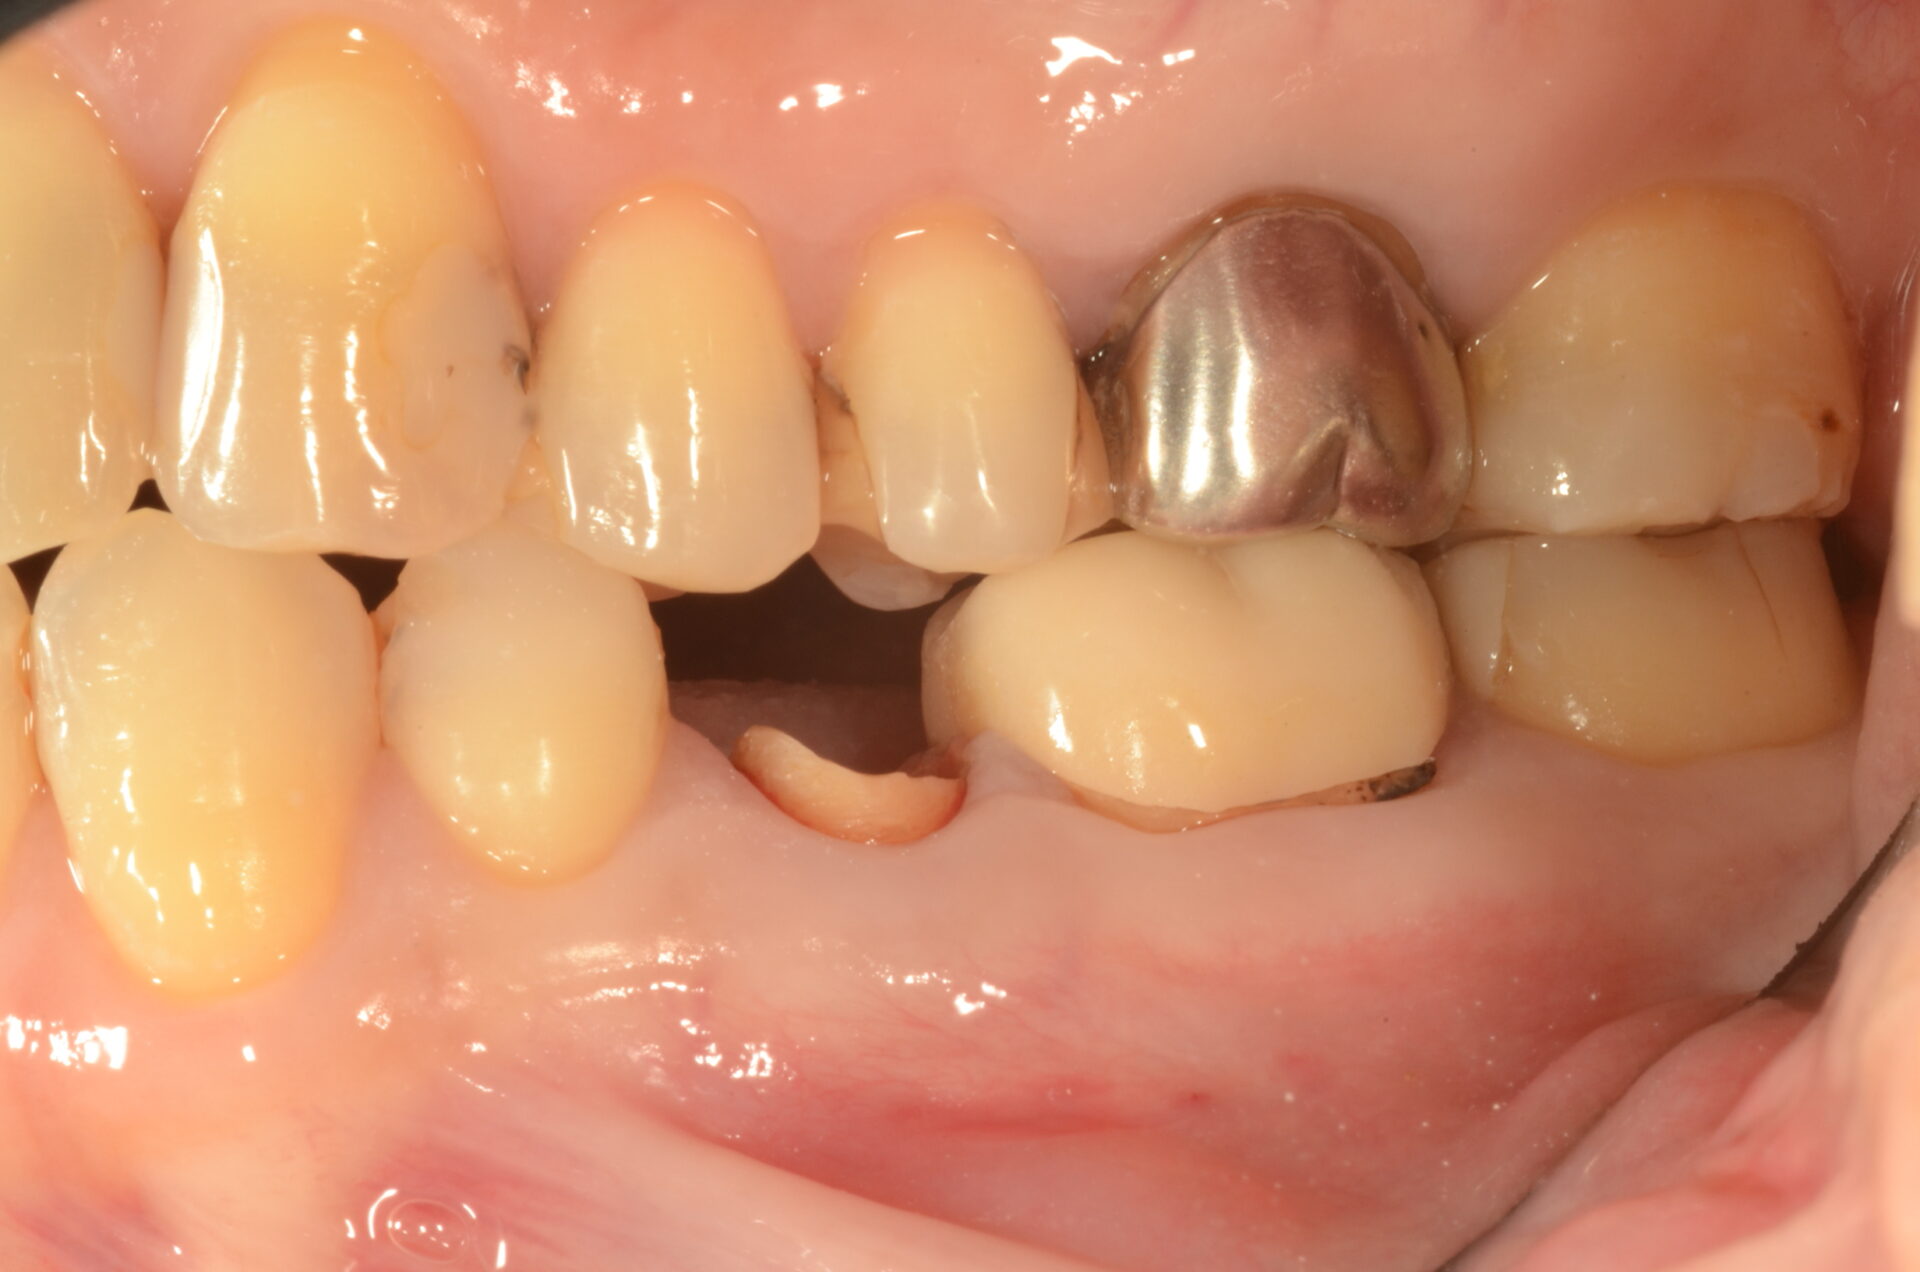

初診時